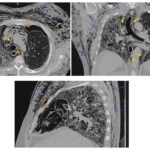

Dentro de los métodos diagnósticos, el neumomediastino se puede diagnosticar mediante radiografías o tomografía computada, donde se va a visualizar la presencia de aire (radiolucidez o hipodensidad lineales) rodeando las estructuras mediastinales. Un signo de muy alta especificidad es el llamado “signo del anillo alrededor de la arteria”, donde se visualiza una imagen radiolúcida o hipodensa en forma de anillo rodeando la arteria pulmonar, principalmente del lado derecho. Este signo ayuda a diferenciar esta entidad del neumopericardio, que puede verse similar en imágenes.

Among the diagnostic methods, pneumomediastinum can be diagnosed using X-rays or computed tomography scans, where the presence of air (linear radiolucency or hypodensity) surrounding the mediastinal structures will be visualized. A highly specific sign is the so-called “ring sign around the artery”, where a radiolucent or hypodense ring-shaped image is visualized surrounding the pulmonary artery, primarily on the right side. This sign helps differentiate this condition from pneumopericardium, which can appear similar on imaging.

De los casos mencionados anteriormente, en el 76,3% (29) el neumomediastino se encontraba asociado a otro signo (10 pacientes presentaban dos signos acompañantes). Dentro de estos se encuentra el enfisema subcutáneo (65%), neumotórax (18%), neumoperitoneo (8%), neumopericardio (2,6%) y enfisema de músculos paravertebrales (2,6%).

También vale la pena mencionar que el neumomediastino es una manifestación poco frecuente (<10%) de la neumonía por COVID-19, principalmente en pacientes que requirieron ventilación mecánica invasiva. En nuestra institución, de los 38 casos encontrados, 7 pacientes (18,4%) tenían el diagnóstico de neumonía por COVID-19, encontrándose en cuidados críticos con intubación orotraqueal.